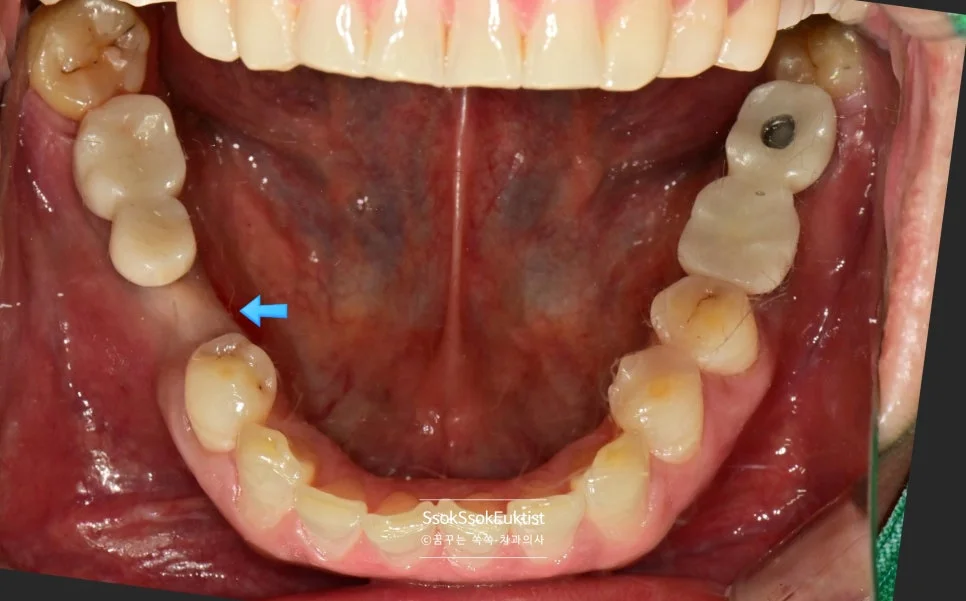

2nd 수면 마취 — 두 번째 수면 마취에서는 오른쪽에 세 개의 임플란트를 식립합니다.

단단하게 유착되어 있는 임플란트를 제거하고 바로 그 자리에 임플란트를 식립하는 고난도 시술인데요^^

2차 수면 마취 — 우측 임플란트 3개 식립 완료 (화살표)

가능한 주변 골보다 2~3mm 깊게 임플란트가 온전히 뼈 안에 잠기게 식립되었다면 잘 심긴 임플란트입니다.

오른쪽은 뼈이식이 많이 들어갔기에 3달의 치유 기간을 가집니다.